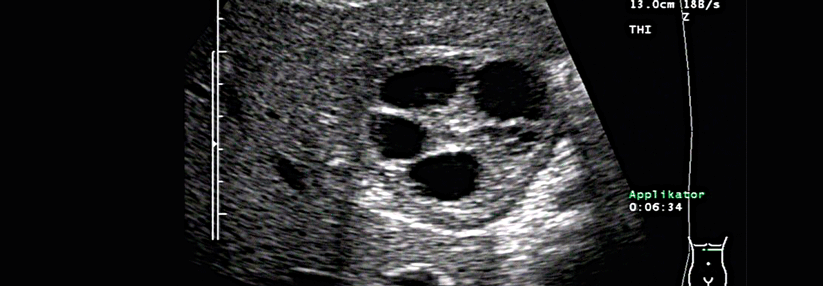

Giardia lamblia existiert in einer aktiven fortpflanzungsfähigen Trophozoitenform sowie in einer Zystenform, die über Monate im Darm überdauern kann und auch für die Übertragung verantwortlich ist. Die Infektion mit den Zysten erfolgt fäkal-oral von Mensch zu Mensch, z.B. durch Trinken von kontaminiertem Oberflächenwasser oder Verzehr verunreinigter Lebensmittel.

Im Duodenum entstehen aus jeder Zyste zwei Trophozoiten, die sich im Jejunum durch Zweiteilung weiter vermehren und sich mit ihren Haftscheiben an das Zottenepithel ansetzen. Der Bürstensaum atrophiert unter diesem „Trophozoitenteppich“, sodass eine Malabsorption entsteht. Im Ileum kapseln sich die Trophozoiten wieder in Zysten…